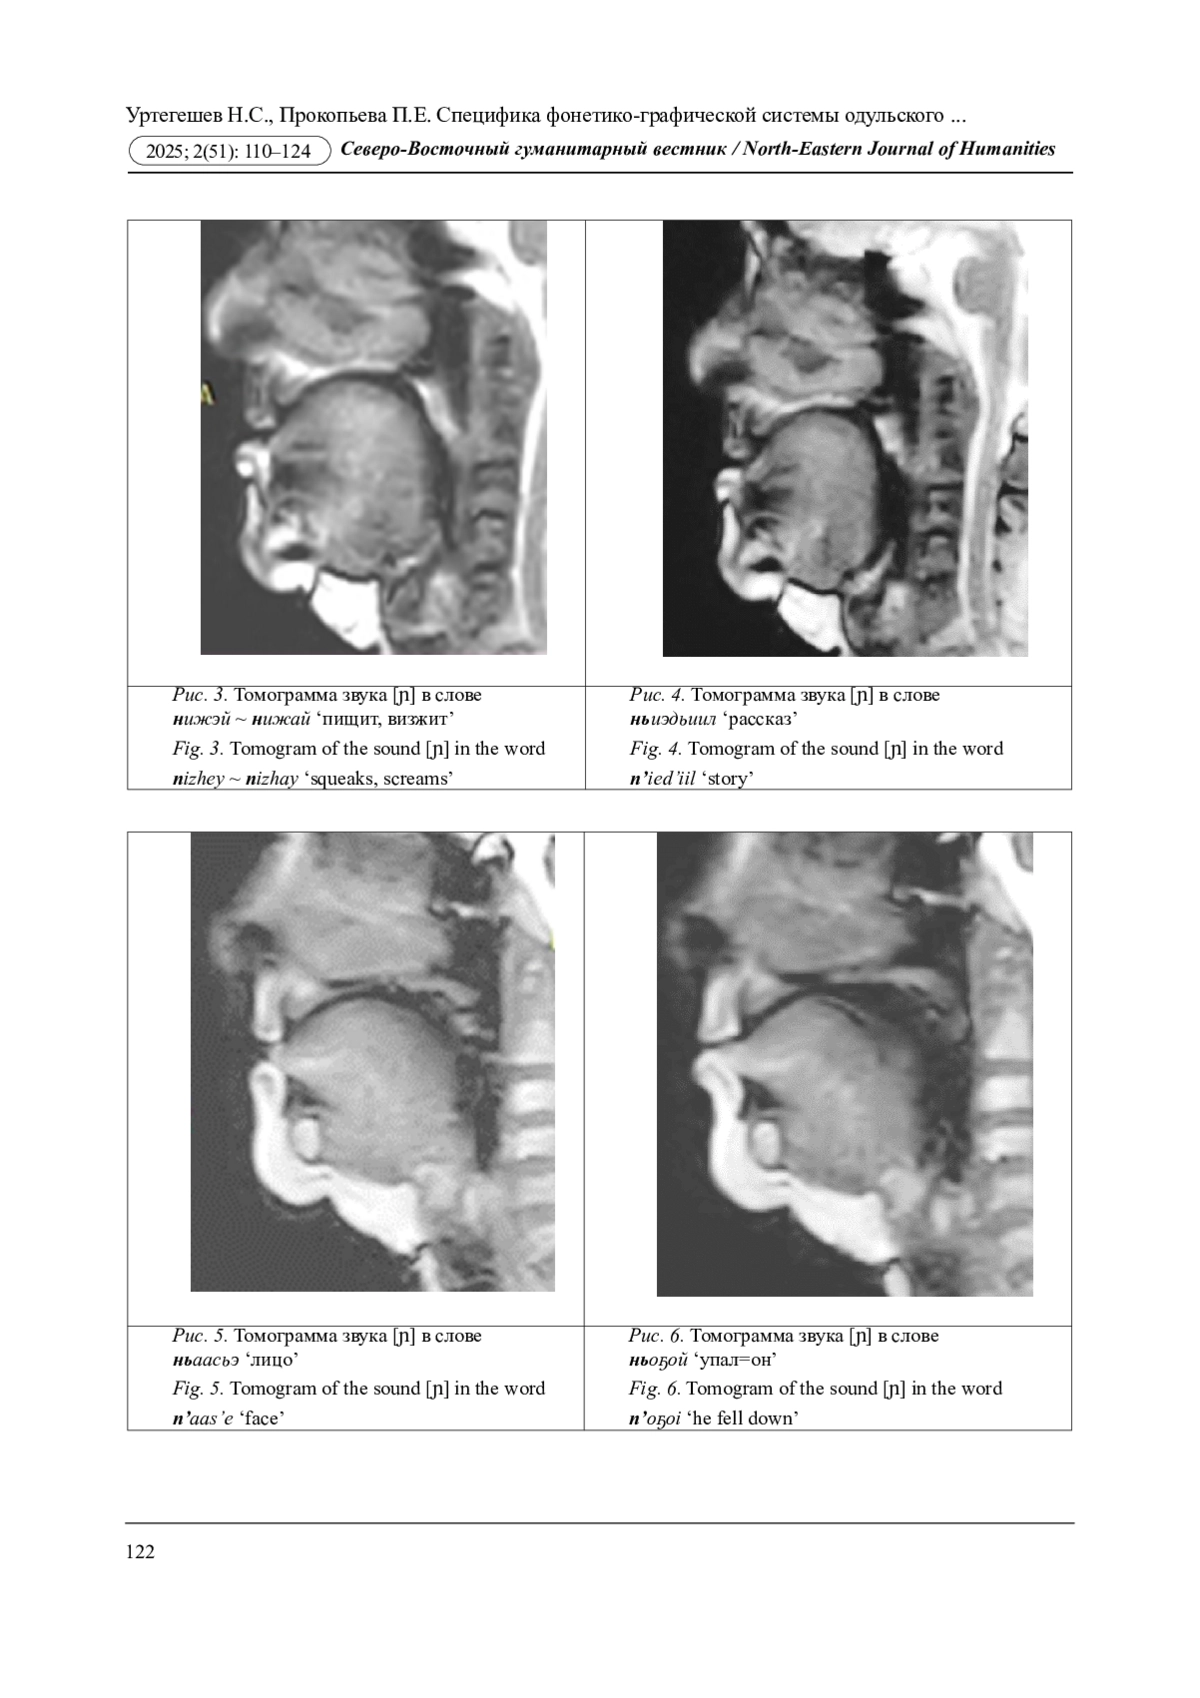

В настоящей работе впервые методами экспериментальной фонетики описываются артикуляционно-акустические характеристики мягких согласных лесного юкагирского, или одульского, языка, обозначаемых на письме Н(ь)1 и НЬ. В ходе анализа лингвистического материала получены следующие результаты: 1) монографом Н(ь) и диграфом НЬ обозначается одна и та же артикуляционная настройка [нOѴ] - мягкая, переднеязычно-среднеязычная фарингализованная, сильнонапряженная; 2) в одульском языке смычные назальные фронтальные (переднего образования) типа «<» противопоставлены не как в русском языке - переднеязычные твердые / переднеязычные мягкие, а переднеязычно-среднеязычные мягкие / переднеязычные интердентальные твердые.